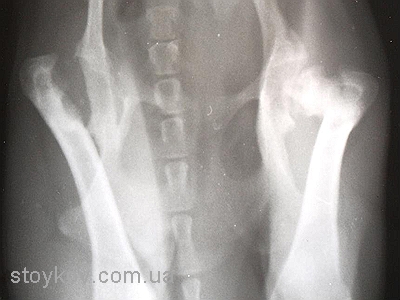

В перші місяці лікування проводиться консервативно. Важливо пам’ятати, що лікарські препарати практично не впливають на перебіг і подальший прогноз захворювання, тому основою консервативного періоду лікування повинно бути утримання тварини в маленькій клітці для іммобілізації кінцівки з метою зменшення зони ураження голівки стегна. Багато ветеринарних ортопедів вважають, що накладання пов’язки для іммобілізації може погіршити стан голівки стегнової кістки при гострому періоді хвороби LCP. Період консервативного лікування також є періодом спостереження, як етап для підтвердження діагнозу (порівняння рентгенівських знімків). Деякі тварини з діагнозом LCP після гострого перебігу хвороби починають опиратися на кінцівку і через півроку-рік функція частково відновлюється. Протягом подальшого життя тварина почувається відносно комфортно. Важливо відмітити, що у однієї тварини на рентгенівському знімку, що був зроблений через 3 роки голівка стегнової кістки була практично відсутня (як після резекції). То виникає запитання, чи варто мучити тварину півроку заради результату, якого можна досягти за два тижні?

Саме тому у більшості випадків вибір залишається за хірургічним лікуванням. Мета хірургічного лікування – зменшення болю, але зважаючи на невеликий розмір тварини, функція прооперованої кінцівки залишається задовільною. Для проведення операції потрібно використовувати остеотом або осциляторну пилку. Використання дротяної пилки не бажано тому, що у такому випадку зріз буде проведено у найвужчому місці шийки, тобто посередині, а потрібно відсікати всю шийку повністю. Не дивлячись на удавану простоту операції дуже важливо провести правильну лінію зрізу шийки стегна і максимально зберегти капсулу суглоба. Після відсікання шийки стегна потрібно ретельно зашити капсулу суглоба. Інколи, для збільшення прошарку м’яких тканин між стегновою кісткою і тазом, використовують техніку м’язового клаптику. Якщо така операція проводиться у собак до 7 кг маси тіла то інтерпозиція частини двоголового мускулу не обов’язкова.